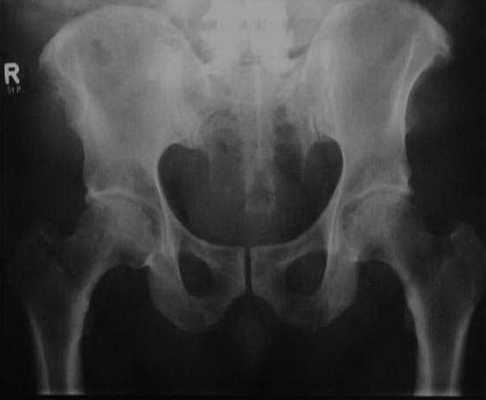

Диффузный идиопатический гиперостоз скелета. Рентгенологическое исследование костей таза демонстрирует щетковидные пролифераты кости в месте прикрепления сухожилий к гребню подвздошной кости, вызванные окостенением фиброзной ткани.